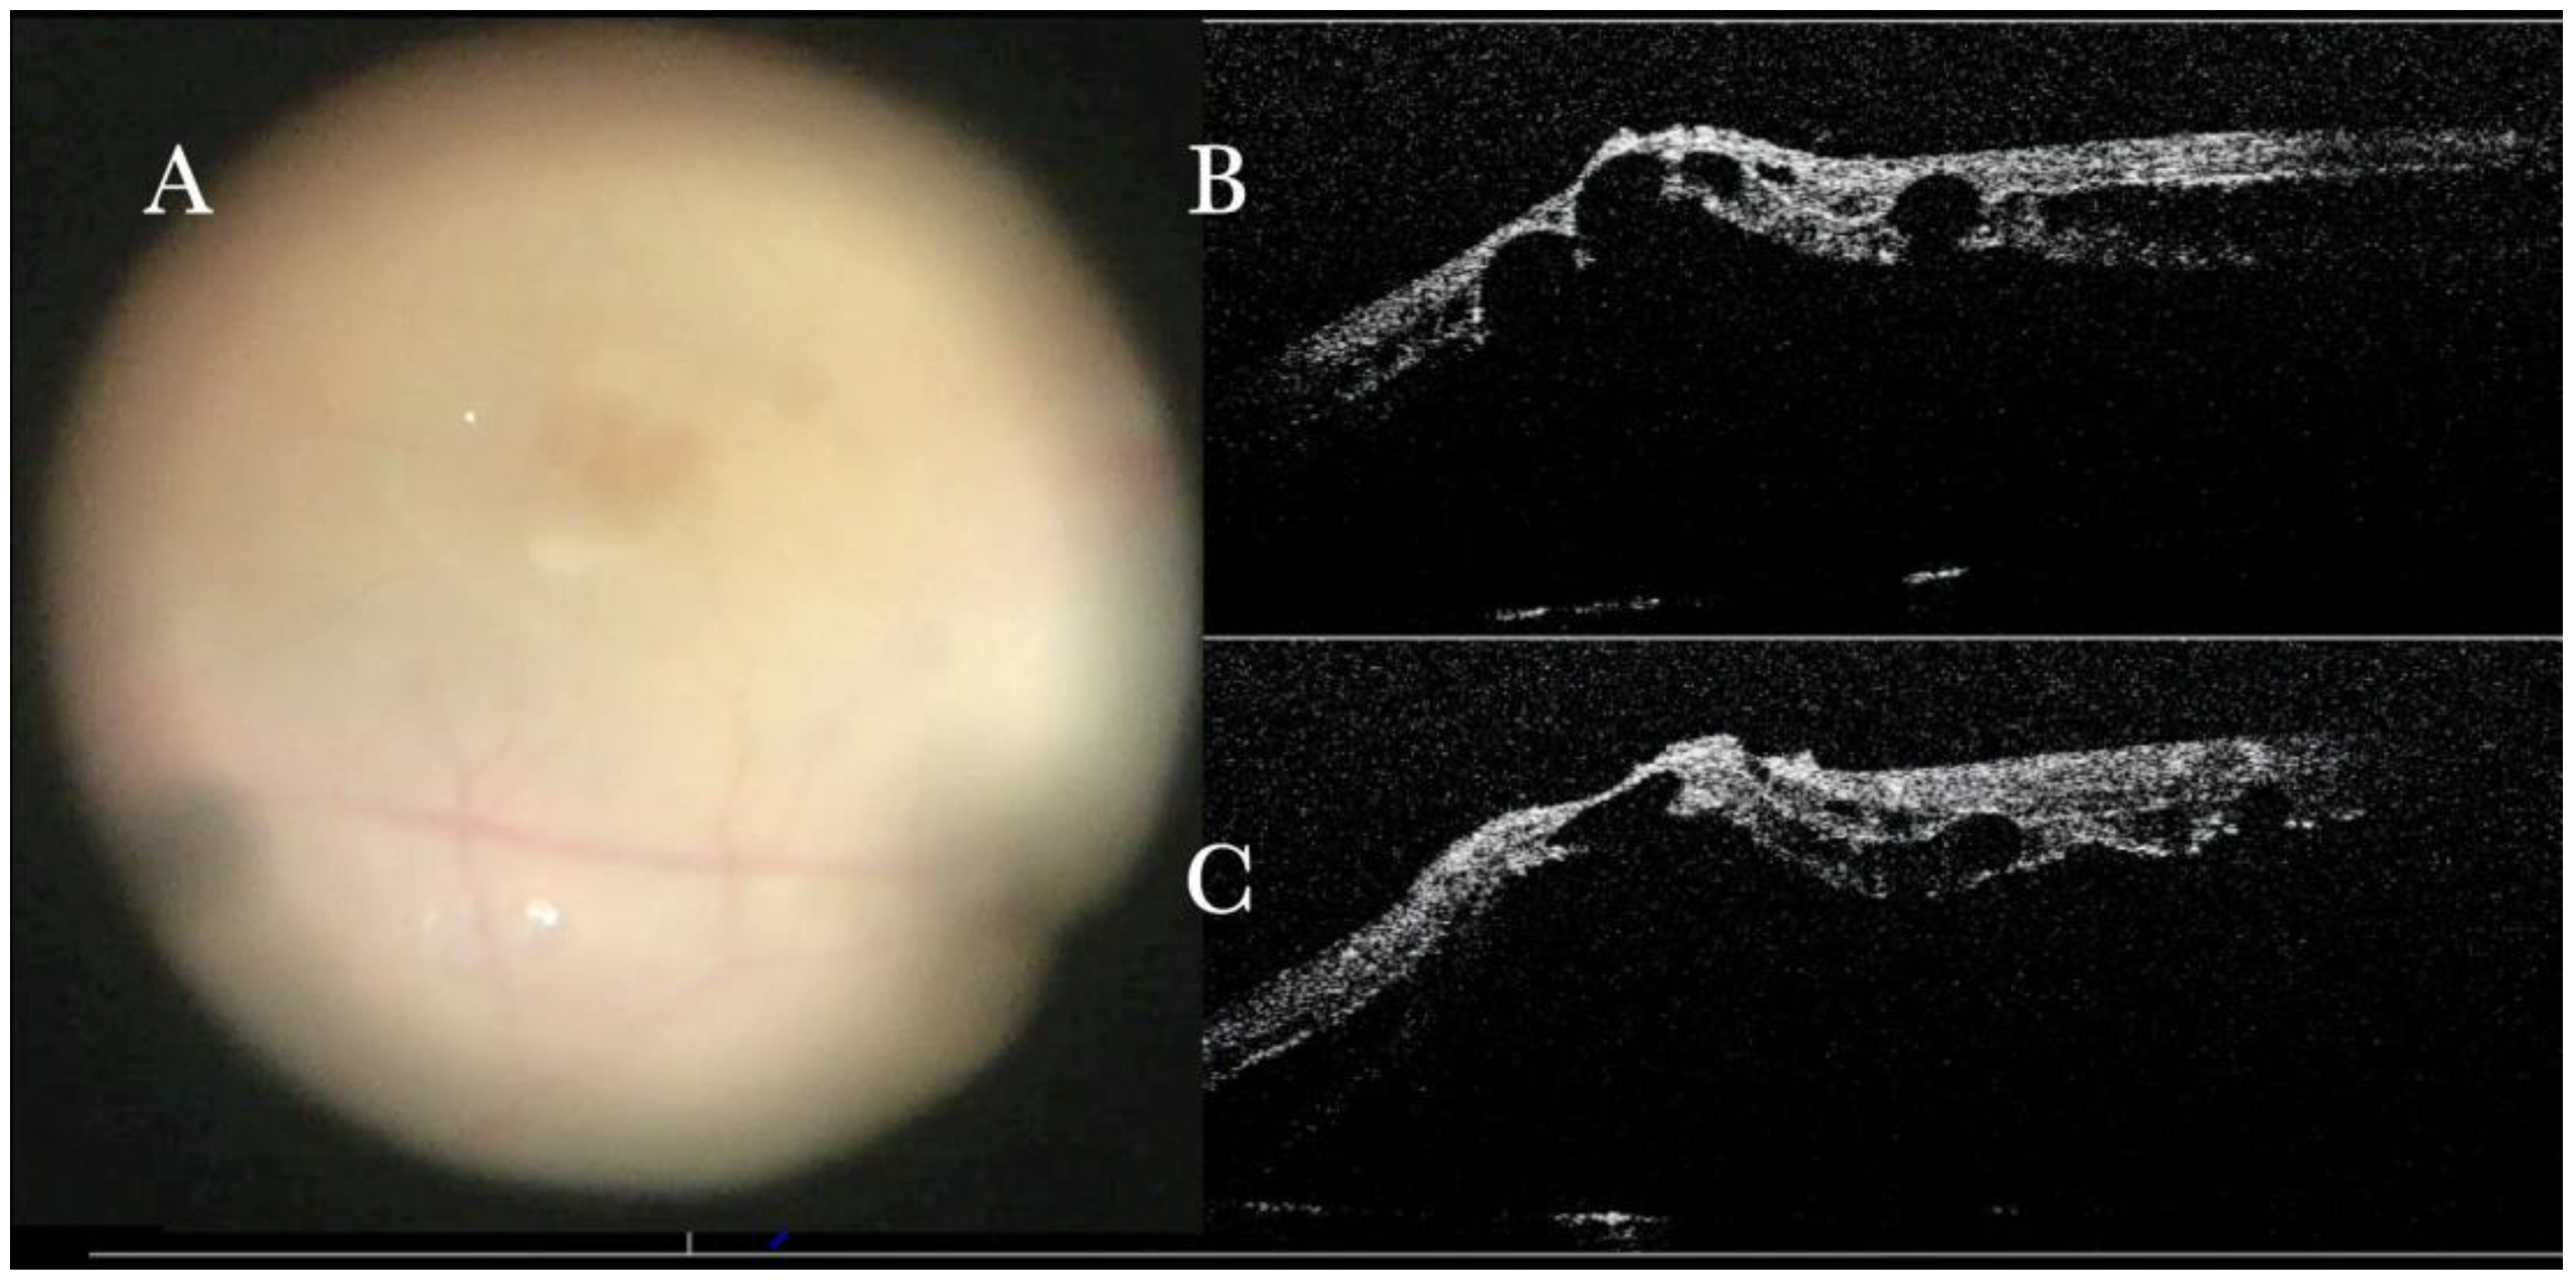

Figure 4.

(A) Microscope view of the macular area during peeling of an epiretinal membrane (ERM). The ERM is elevated. (The white box indicates the field-of-view of the OCT scan, the green circle within the white box represents the effective working distance and green and blue lines within the green circle show the vertical and horizontal scan planes). (B) Intraoperative optical coherence tomography (i-OCT) B horizontal (green arrow) scan during peeling. The ERM is elevated, and the macular profile is preserved where the ERM has been peeled. (C) i-OCT B vertical (blue arrow) scan during peeling. The ERM is elevated. The inner limiting membrane (ILM) is stretched and elevated where the ERM is peeled. The i-OCT allowed us to see the double simultaneous peeling of ERM and ILM.